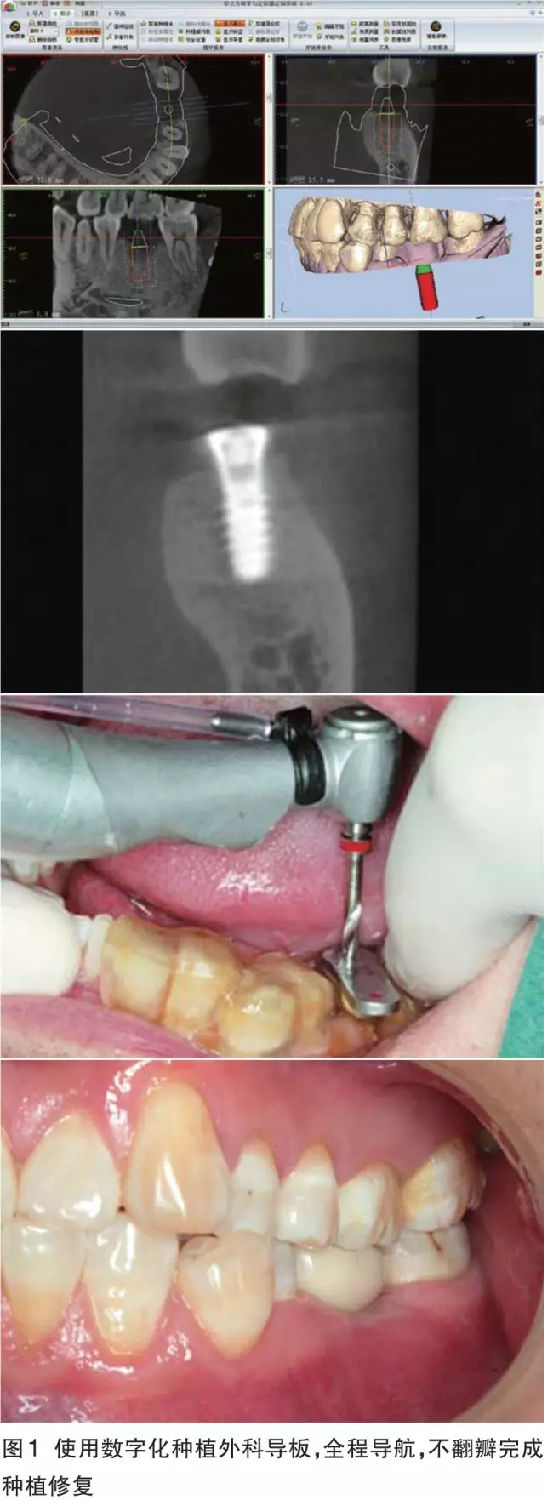

數(shù)字化導(dǎo)板的優(yōu)勢 對于軟硬組織充足、解剖條件好,導(dǎo)板能夠容易精準就位的病例,如果患者經(jīng)濟條件允許,全套的數(shù)字化解決方案可以預(yù)見性地、完美地、即刻恢復(fù)缺失牙患者的美觀和功能。同時可以幫助無經(jīng)驗的醫(yī)師規(guī)避重要解剖結(jié)構(gòu)、減少外科風(fēng)險、獲得術(shù)前根據(jù)修復(fù)效果設(shè)計的最佳種植體位置(圖1)。